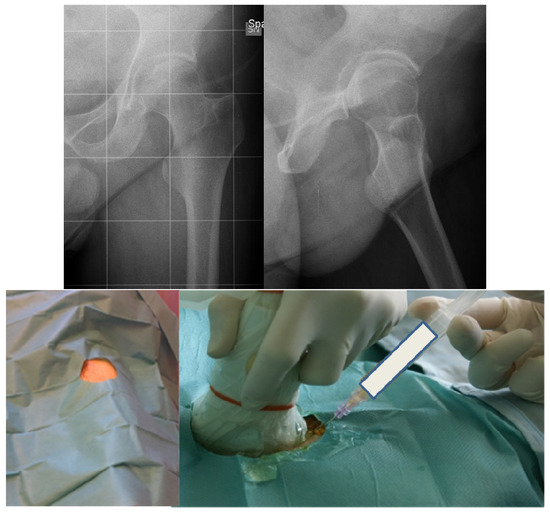

In the case of failure of a primary implant, the use of modular revision implants and the principles of tissue engineering may be very useful to obtain a good osteointegration and an adequate reconstruction of the joint (Figure 5).

Figure 5. (a) Primary total hip arthroplasty (THA) of a 47-year-old severe haemophilia A patient; (b) Aseptic failure of the implant with loosening; (c) Revision with modular acetabular and femoral prostheses and acetabular reconstruction by biological composite (heterologous bone chips enriched with a concentration of autologous mesenchymal cells harvested from the iliac crest) and a trabecular metal wedge fixed by screws; (d) Four years after revision surgery, optimal integration of the components.